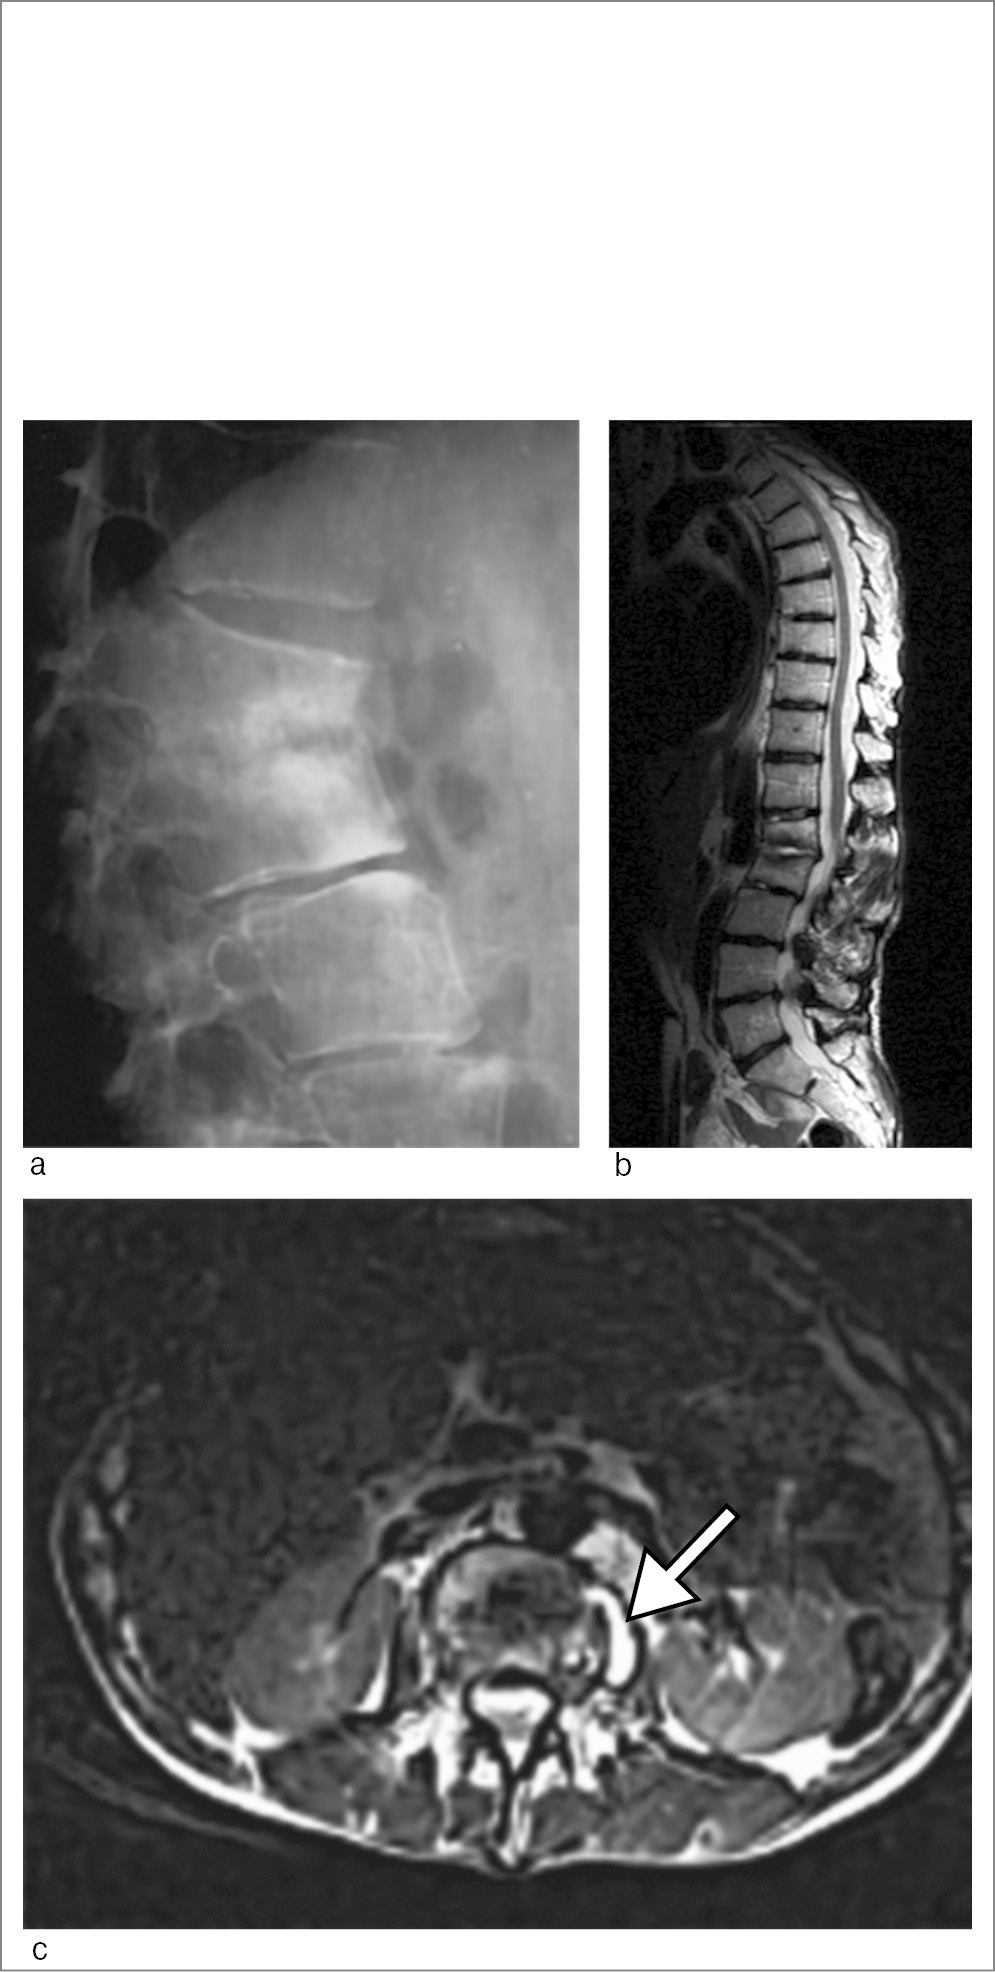

Спондилиты (спондилодисциты) могут вызываться и другими бактериями. Визуализационная картина в этих случаях не имеет каких-либо особенностей и не отличается существенно от туберкулезного или бруцеллезного поражения позвоночника (рис. 8).

Рис. 8. Пациентка Б., 33 года. Диагноз – остеомиелит тел позвонков LI и LII вероятно стафилококковой природы: a – рентгенограмма поясничного отдела позвоночника: деструкция смежных отделов LI и LII; b – МРТ (сагиттальная плоскость, режим Т2): дисцит в сегментах ThXII–LI и LII–LIII; c – МРТ (аксиальная плоскость, режим T2-STIR): паравертебральное жидкостное образование размерами 2,3×1 см (стрелка) в области левой подвздошно-поясничной мышцы (натечник).